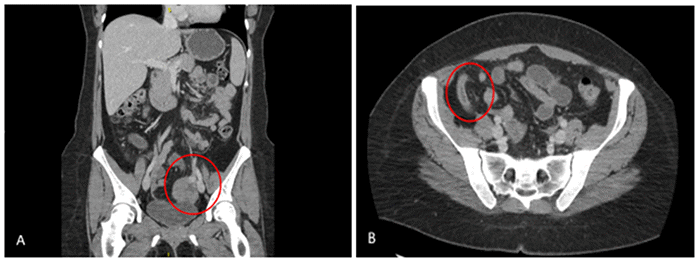

Workup in the emergency department with computed tomography imaging of the abdomen and pelvis (Figure 1) showed: (A) a heterogeneously enhancing high left adnexal mass without a separate left ovary identified; and (B) a dilated appendix demonstrating increased mucosal enhancement and adjacent fat stranding, consistent with acute appendicitis.

Figure 1. Abdominopelvic CT Scan. Published with Permission

(A) Heterogeneous enhancing mass in the left adnexal region. No separate left ovary is identified. (B) Dilated appendix with increased mucosal enhancement and surrounding fat stranding (suggestive of acute appendicitis)